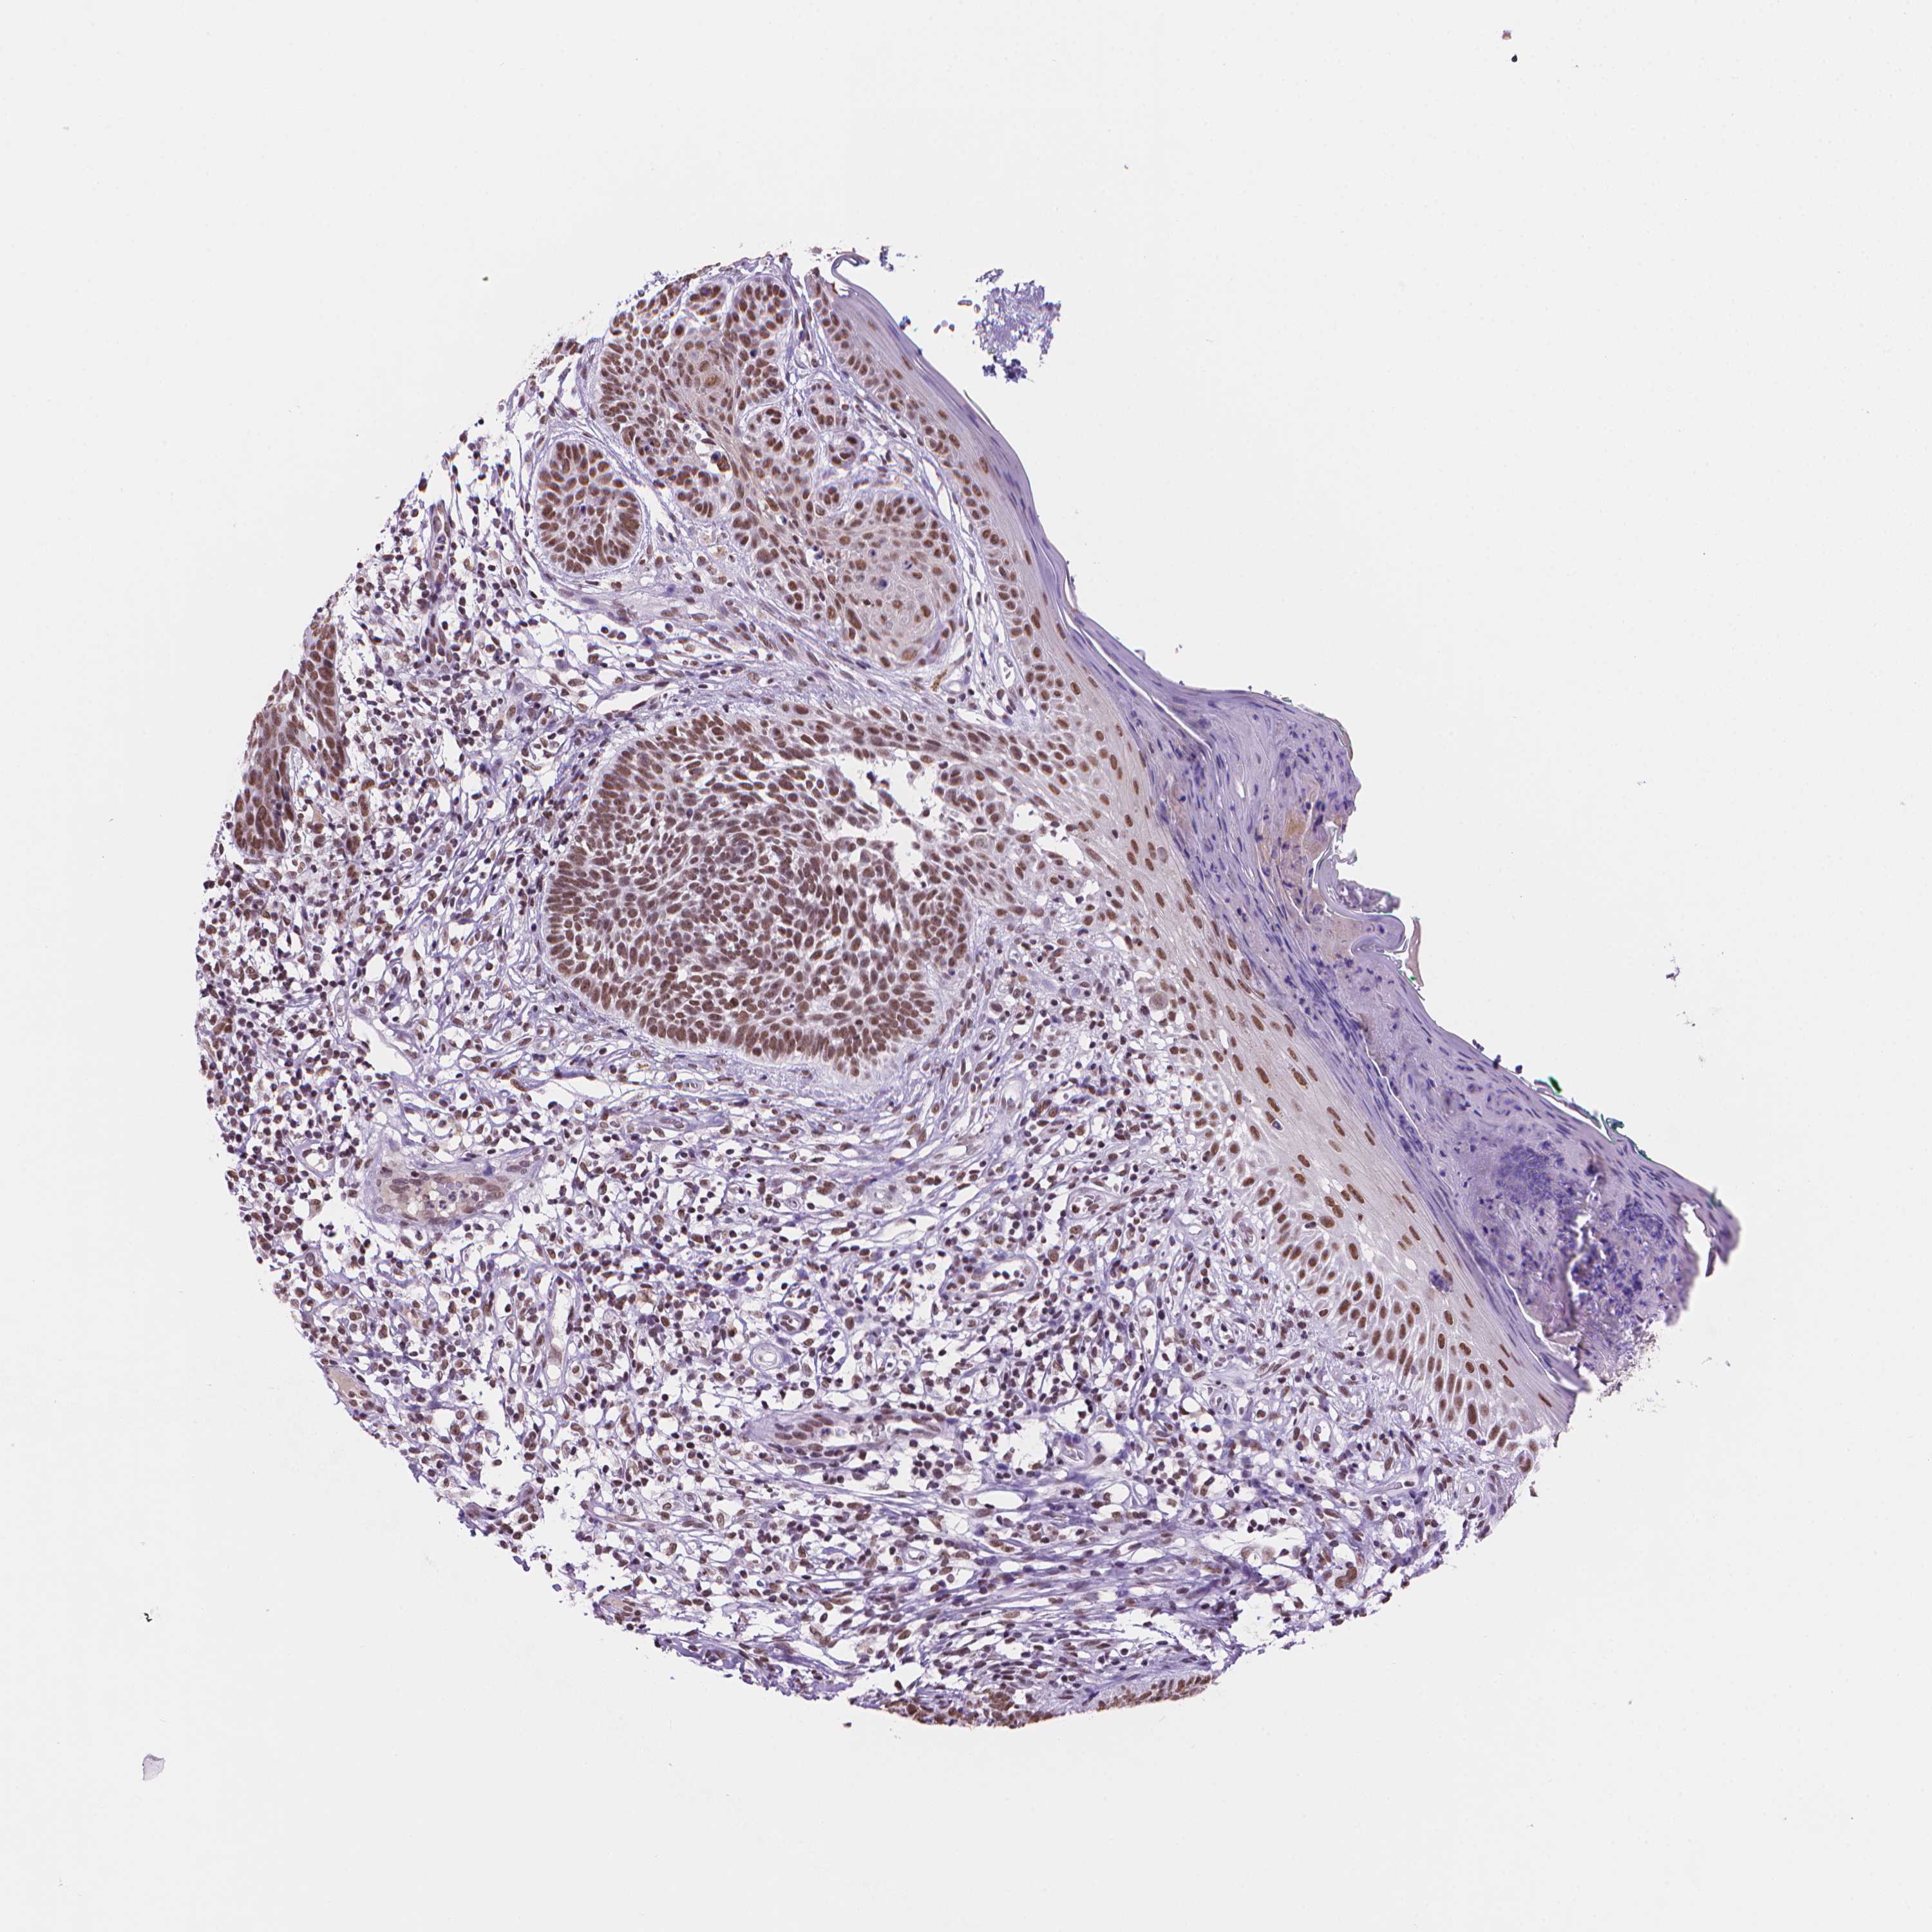

Basal cell and squamous cell cancer

SKIN CANCER - Protein expressioni

A mouse-over function shows sample information and annotation data. Click on an image to view it in a full screen mode. Samples can be filtered based on level of antibody staining by selecting one or several of the following categories: high, medium, low and not detected. The assay and annotation is described here.

Each image is clickable and will lead to virtual microscopy that enables deeper exploration of all samples and also displays staining intensity scores, fraction scores and subcellular localization as well as patient and tissue information for each sample.

Antibody HPA066010

Staining

High

Medium

Low

Not detected

Intensity

Strong

Moderate

Weak

Negative

Quantity

>75%

75%-25%

<25%

None

Location

Nuclear

Cytoplasmic/membranous

Cytoplasmic/membranous,nuclear

Basal cell carcinoma

Squamous cell carcinoma, NOS